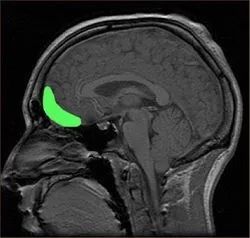

图源:zh.wikipedia.org

左边为正常人的(法隆教授的儿子),右边是罪犯/像罪犯一样的(法隆教授自己的)